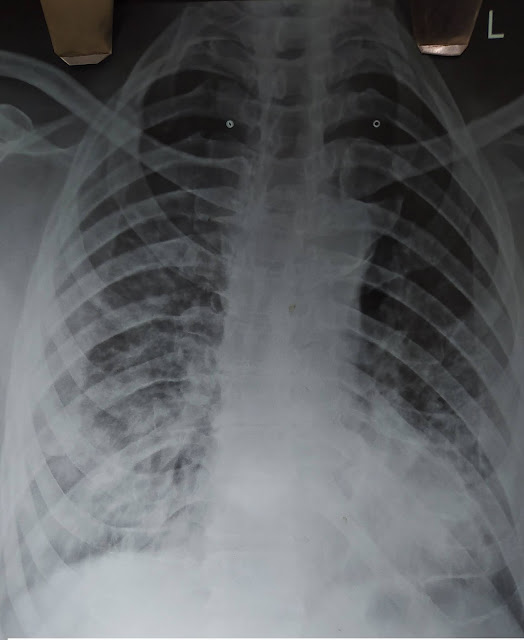

You organize a portable X- ray chest which is shown below .

Severe ARDS secondary to SARS-COVID. The history is suggestive of Covid -19 associated Acute Respiratory Distress Syndrome and Chest X -ray is also strongly suggestive of SARS Covid ARDS.